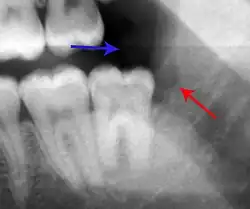

The periodontal ligament becomes inflamed and there may be pain when biting or tapping on the tooth. On an X-ray, bone resorption appears as a radiolucent area around the end of the root, although this does not manifest immediately.[10]: 228 Acute apical periodontitis is characterized by well-localized, spontaneous, persistent, moderate to severe pain.[6]: 125–135 The alveolar process may be tender to palpation over the roots. The tooth may be raised in the socket and feel more prominent than the adjacent teeth.[6]: 125–135

- Radiographs utilized to find dental caries and bone loss laterally or at the apex.

Decay (green) with apical abscess (blue) -

Gutta-percha point indicating abscess origin